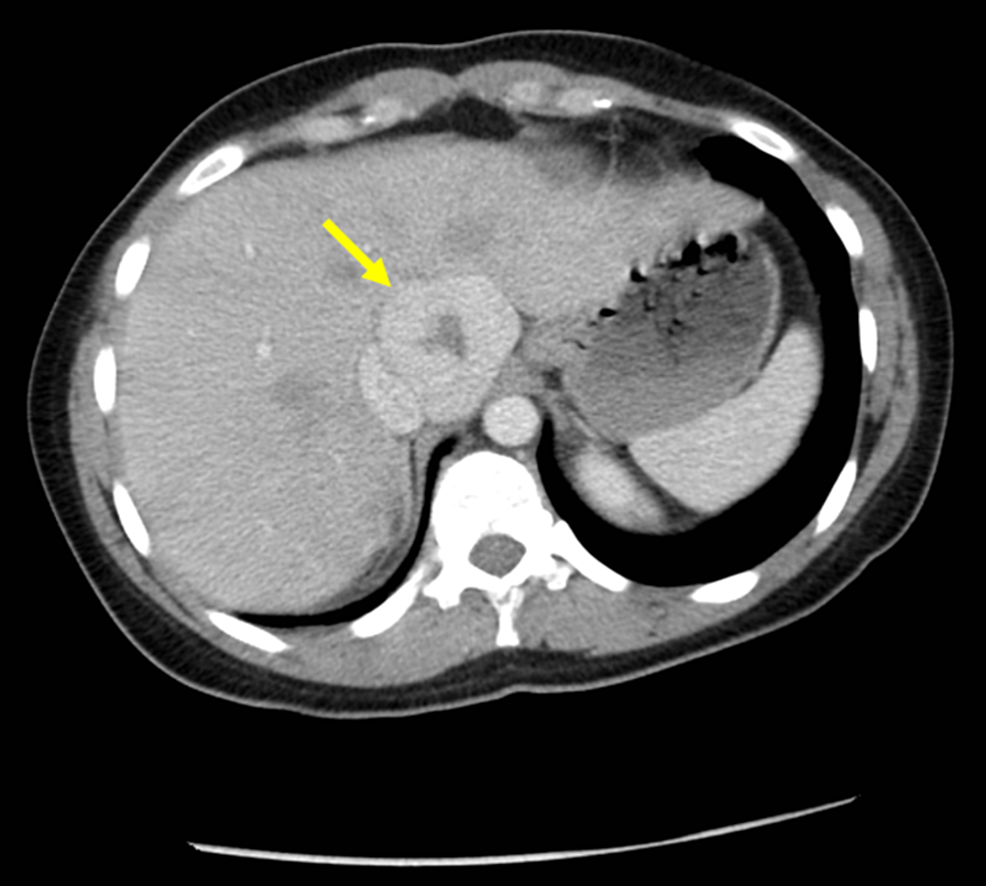

Figure 1 from Multiple FNHLike Lesions in a Patient with Chronic Budd

Figure 1 from Multiple FNHLike Lesions in a Patient with Chronic Budd Mri Eovist Fnh Find out how hepatospecific contrast agents can help to characterize fnh and. Fnh is the second most common benign lesion in the liver (after. Liver mri with eovist is reserved primarily for diagnostically characterizing a liver lesion as focal nodular hyperplasia (fnh). It is used for liver imaging to assess vascularity and function of liver lesions. Six criteria for typical. Mri Eovist Fnh.